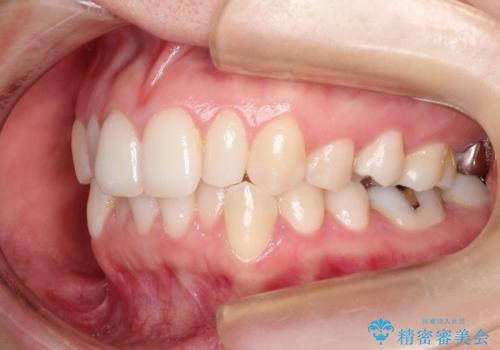

初診時の歯並びの状態としては、上下ともに前歯部の中等度のがたつきがあり、特に左上の前歯が1本内側に入り込んでしまっている状態でした。

また、2mm程度の正中離開がありました。

抜歯なし/インビザラインによるマウスピース矯正にて治療を行いました。

内側に入り込んでしまっている歯を出してくることに非常に時間がかかりましたが、一度歯を歯茎の方へ押し込みそして前へ出してくる2段階の治療を行いました。

見た目、嚙み合わせ及び、治療期間や施術内容に大変ご満足いただきました。